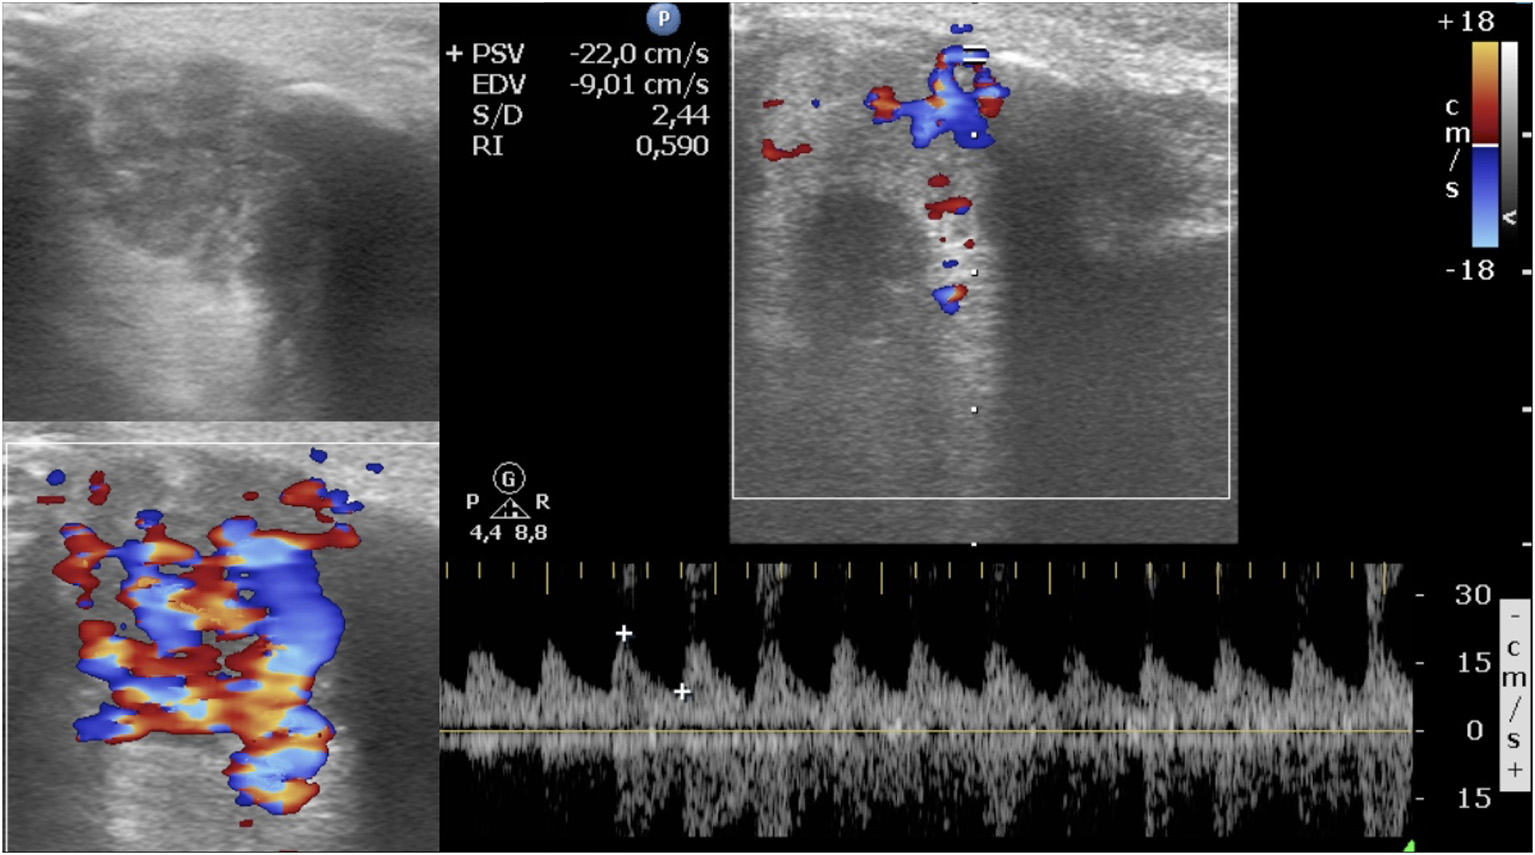

FIGURE 2

www.frontiersin.org

Figure 2. The same infantile hemangioma of Figure 1. Latest ultrasound evaluation with detectable color Doppler signals after 3 months of oral propranolol. Post-treatment images show a smaller mass with heterogeneous echogenicity; at color Doppler, the vascularization is reduced, and the resistive index is 0.57.

A total of 64 IHs in 60 patients were retrospectively analyzed. Four children had two IHs. All IHs had a good clinical response to oral propranolol. A good clinical result is defined as a complete or almost complete or partial regression of IH. The infants were 19 male and 41 female. The age at diagnosis was between 0.9 and 8.3 months, with an average age at diagnosis of 3.5 months. The average age of initiation of treatment was 5 months (Tables 1, 2). Twenty out of 64 lesions were excluded from the evaluation of RI values because, at the ultrasound examination after 1 month of therapy, they did not show significant vascular signals for sampling. The RI values where then compared in 44 lesions with at least two significant samplings of RI and evaluated until the disappearance of the color Doppler signals. Among these 44 lesions, 24 were superficial IHs, 13 mixed his, and seven deep IHs. In 44 lesions, we recorded the values sampled in each IH and calculated the mean RI value. We compared the mean RI values at baseline with the mean RI values at the last control during treatment, in which it was possible to sample the vascular signals. The last ultrasound examination in which it was possible to detect and sample RI values was the evaluation at the first month after therapy in 14 lesions, at the third month of therapy in nine lesions, and at the sixth month of therapy in 21 lesions. In the 44 lesions compared, we did not find statistically significant variations in the mean RI values between the baseline control (0.57) and the values recorded at the last post-treatment control, in which there were appreciable vascular signals (0.58) (Table 3) (Figures 1, 2).